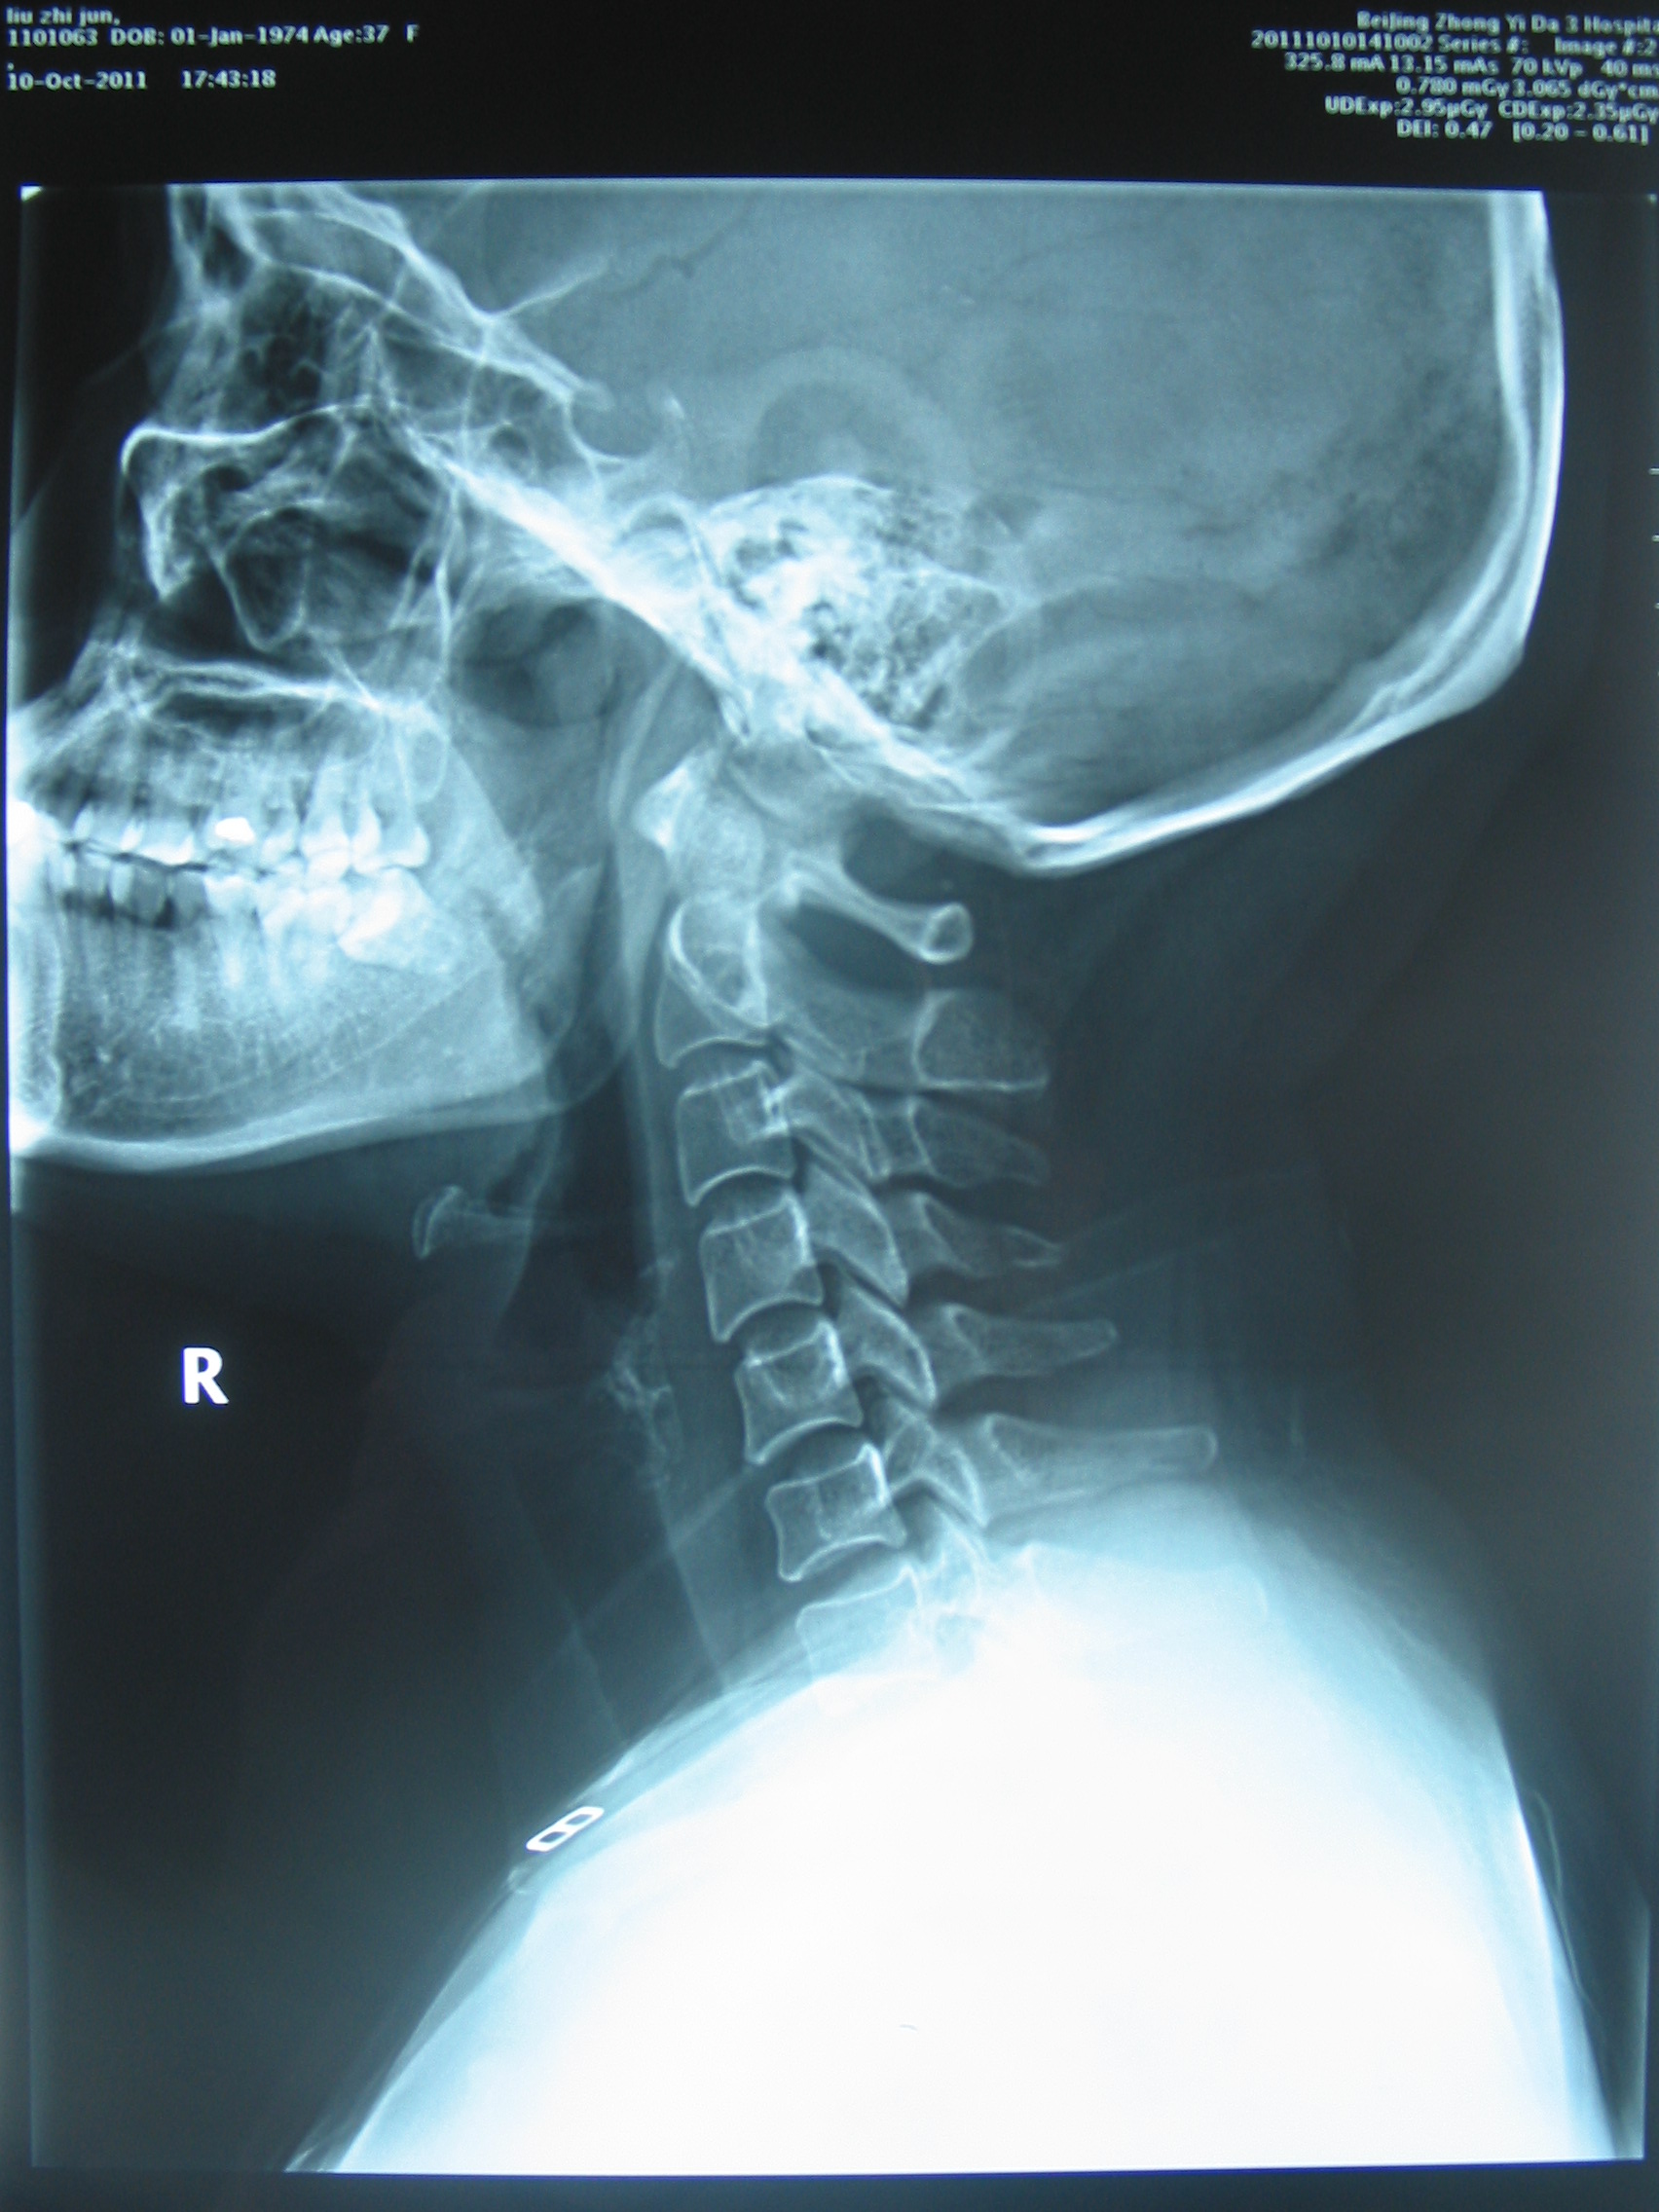

患者,女性,37岁,诉晚间卧床看电视过久,次日清晨头晕、恶心严重,遂至我院急诊就诊。予扩张血管、止吐等药物对症治疗,无明显疗效。查颈椎X线片,请我科门诊会诊。阅片:颈椎曲度异常,可见颈椎小关节紊乱征象(图X线片1,2, 颈椎正侧位治疗前(左侧))。予颈椎不定点旋转手法复位治疗,头晕恶心立即大部分缓解。隔日门诊复查仅残留偶发眩晕症状,复用旋转手法治疗,症状完全消失,复查X线,颈椎小关节紊乱已至正常(图X线片1,2,颈椎正侧位治疗后(右侧)),随访1月未见复发。

图1X线片